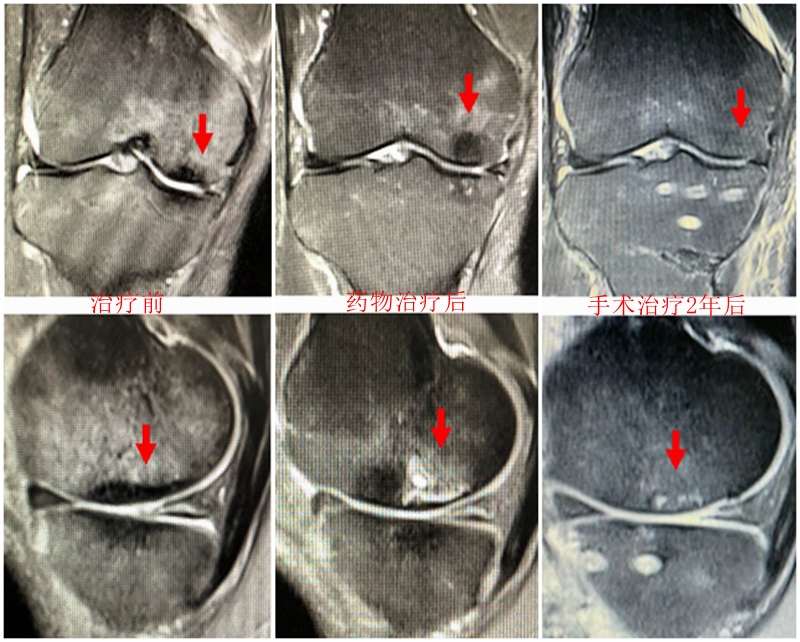

病例:女,65岁,主诉左膝关节内侧疼痛2月余。2017年11月X光未见左膝骨质异常。MR见股骨内侧髁骨坏死,半月板相对突出百分比(RPE)28.3%,合并内侧半月板后根部撕裂,矢状位病变区域前后径为11.67mm,关节线会聚角2.68°

予消炎止痛药物口服、静滴唑来膦酸钠注射液,避免负重6周,后改部分负重,12周后全负重。

2018年2月复查MR见骨髓水肿明显吸收,坏死灶边界清晰,半月板相对突出百分比(RPE)28.92%

2018年6月复查MR见骨髓水肿基本完全吸收,坏死区修复良好,半月板相对突出百分比(RPE)38.54%,患者临床症状消失。

提示坏死好转了,但半月板突出进展了,膝关节的退变加重了。